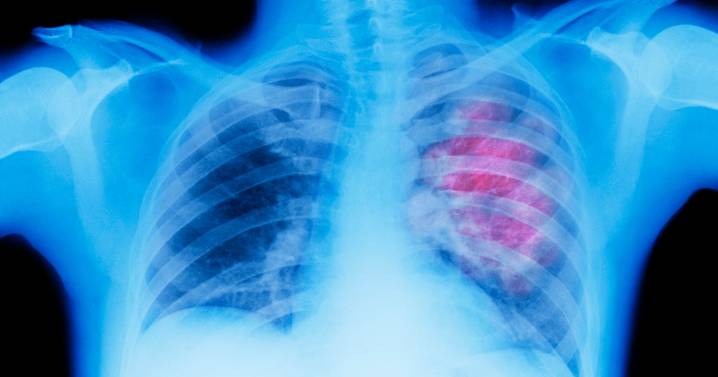

Lung cancer is the leading cause of cancer-related deaths in the United States.

As we start Lung Cancer Awareness Month, a new report shows where we stand in fighting against the disease, including in Pennsylvania.

This is revealed in the new State of Lung Cancer report released by the American Lung Association, with both national and state-by-state data.